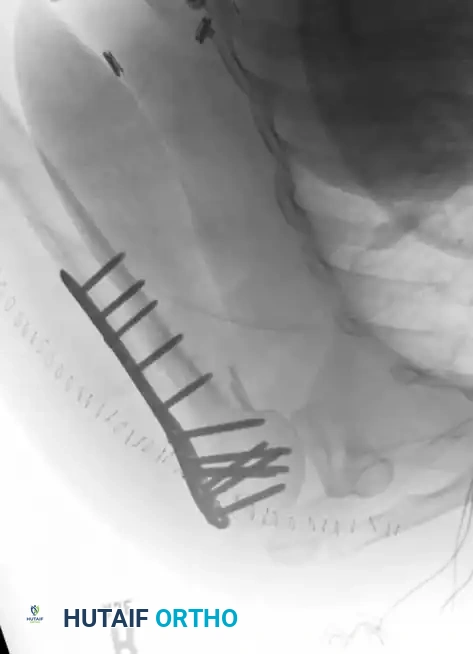

External Fixation of Clavicular Fractures

While intramedullary fixation and superior/anteroinferior plating remain the gold standards for displaced midshaft clavicle fractures, external fixation is a highly specialized technique reserved for specific indications, such as open fractures with severe soft-tissue compromise or infected nonunions.

Fig. 54-6 Pin placement in external fi xation of clavicular fractures. (From Schuind F, Pay-Pay E, Andrianni Y, et al: External fi xation of the clavicle for fracture or non-union in adults, J Bone Joint Surg 70A:692, 1988.)

🔪 Surgical Technique 54-3: External Fixation of the Clavicle

1. Exposure: Expose the fracture through a limited curvilinear incision centered over the defect.

2. Debridement: Meticulously débride the wound and fracture site if the injury is open. Crucial Pitfall: Do not strip the periosteum, as the clavicle relies heavily on its periosteal blood supply for union.

3. Neurovascular Protection: In exposing displaced fracture fragments, use extreme care to avoid injury to the subclavian neurovascular structures and the pleural dome lying immediately beneath the middle third of the clavicle.

4. Pin Insertion: Predrill and insert two noninterrupted, threaded, 3-mm, C-model, Blount-type Hoffman pins (or modern equivalents) through the wound into each fragment.

* Medial Pins: Insert from anterior to posterior in an ascending or horizontal direction to strictly avoid the pleural dome.

* Lateral Pins: Insert from superior to inferior in an anterior or almost vertical direction.

5. Frame Assembly: Reduce the fracture under direct vision or fluoroscopy, and connect the pins with a simple half-frame construct.AFTERTREATMENT: Postoperative management is similar to that described for intramedullary fixation of the clavicle, with the critical addition of routine, meticulous pin site care to prevent superficial tract infections.